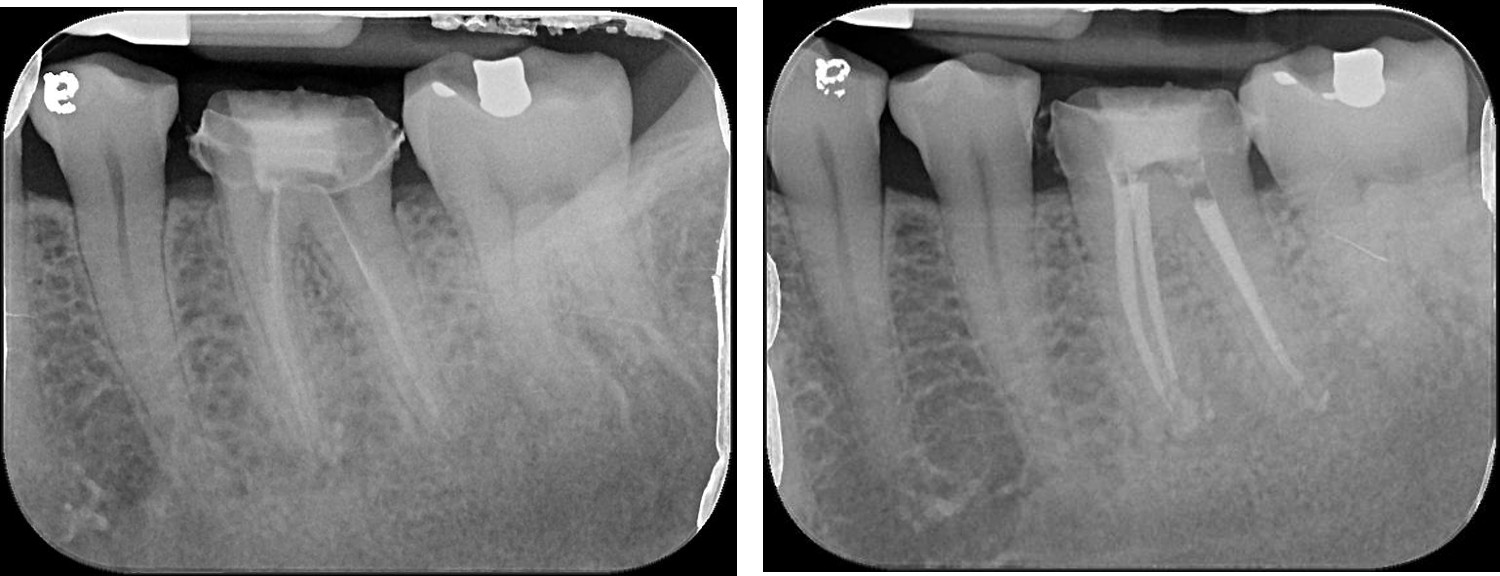

顯微根管治療-根管治療不完全-#36

根管治療

非手術根管治療